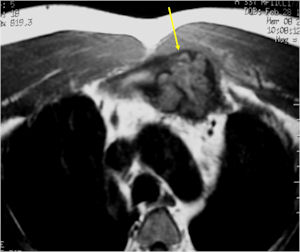

MRI:

- Also useful in determining extent

- There is often extensive edema around the tumor in the surrounding bone and soft tissues that can lead to a misdiagnosis of a malignant tumor.

- Aggressive osteoblastomas are usually larger than a conventional osteoblastoma and have been reported to be up to 8.5 cm in diameter.

- Most have a similar radiographic appearance as a conventional osteoblastoma and have well defined margins, variable amounts of mineralization and peritumoral sclerosis. They occasionally have radiographic characteristics consistent with malignancy.